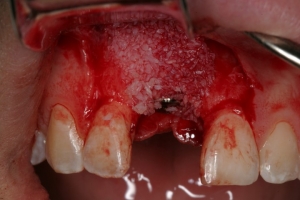

ביצוע ההשתלה עם עיבוי העצם (אוגמנטציה)

קיבוע ממברנה מעל תחליף העצם (הממברנה היא מעין "גדר הפרדה" או מעין פלסטר קטן המגן על אזור תחליף העצם ומאפשר לתאי העצם להתחדש ללא הפרעה)